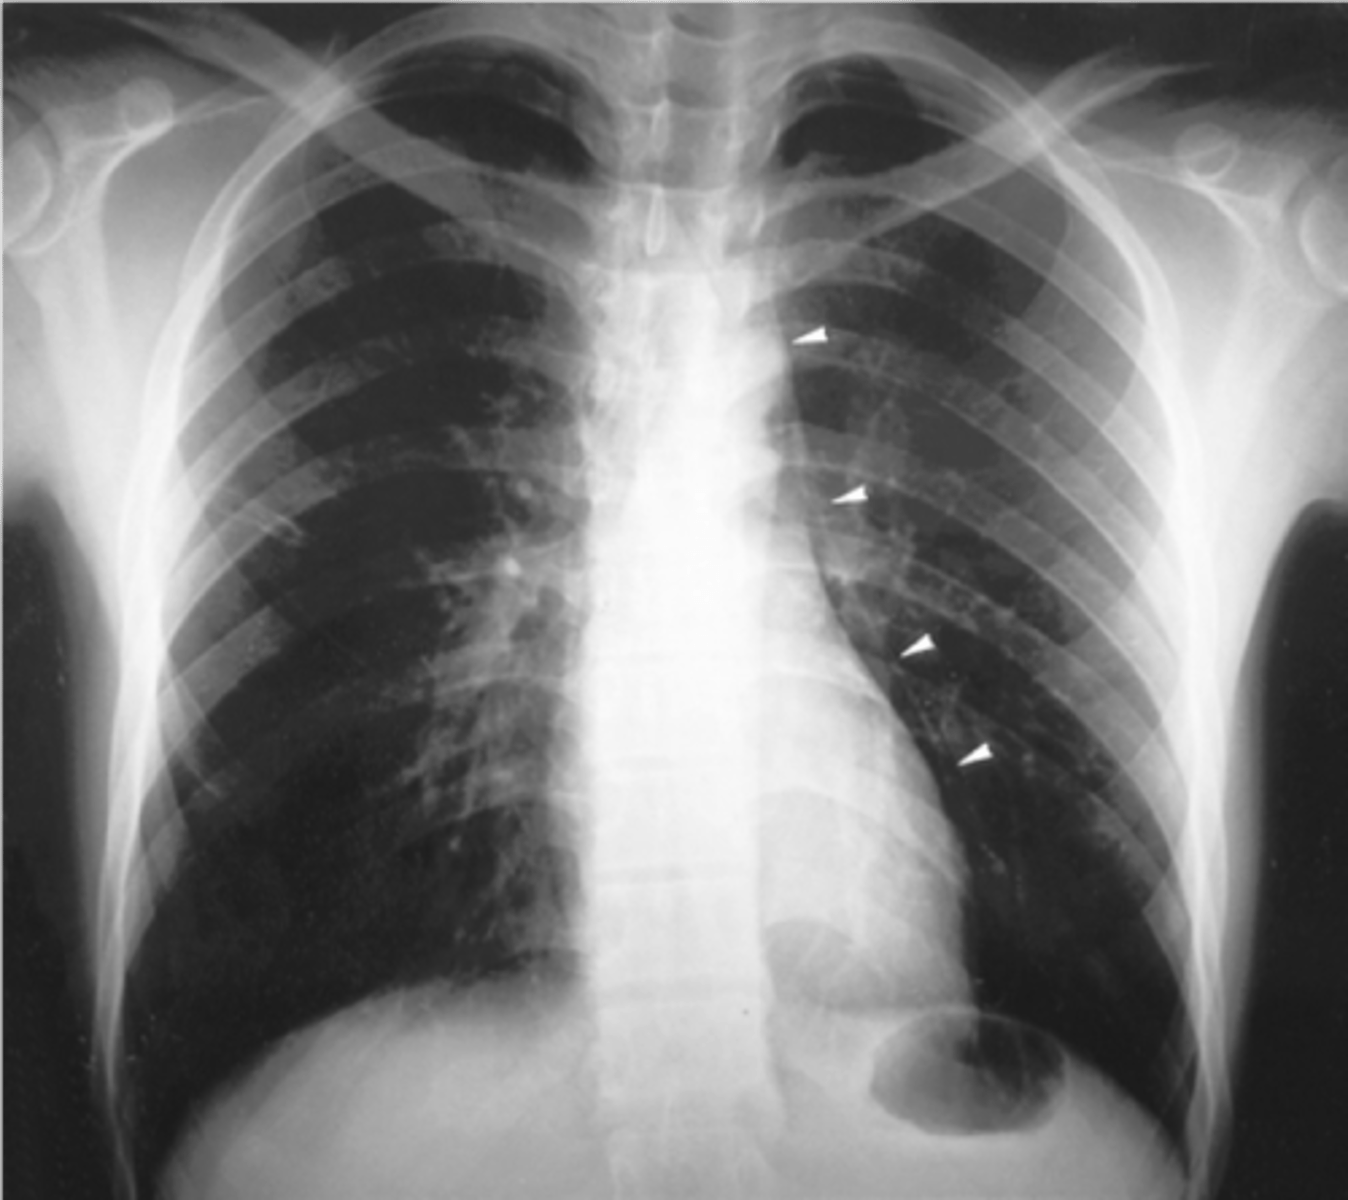

Suspect ___ in pts who have evidence of atherosclerotic vascular dz, present with abd pain followed by bloody diarrhea, and have minimal abdominal exam findings.

Ischemic colitis

- Splenic flexure most common (supplied by end arteries)

- vulnerable to ischemia during systemic hypotension in "water-shed" areas

- X-ray show "thumb printing"